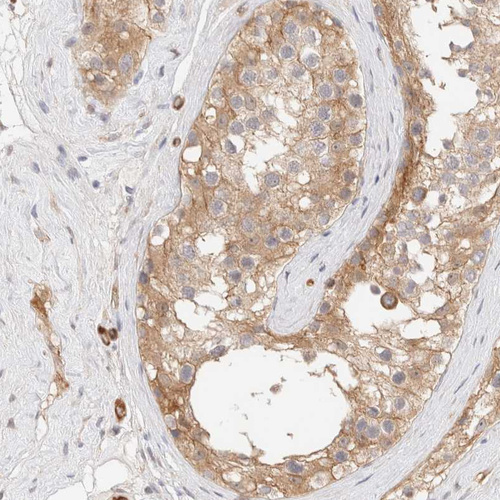

Immunohistochemistry analysis in human skeletal muscle and liver tissues using HPA024059 antibody. Corresponding LMCD1 RNA-seq data are presented for the same tissues.